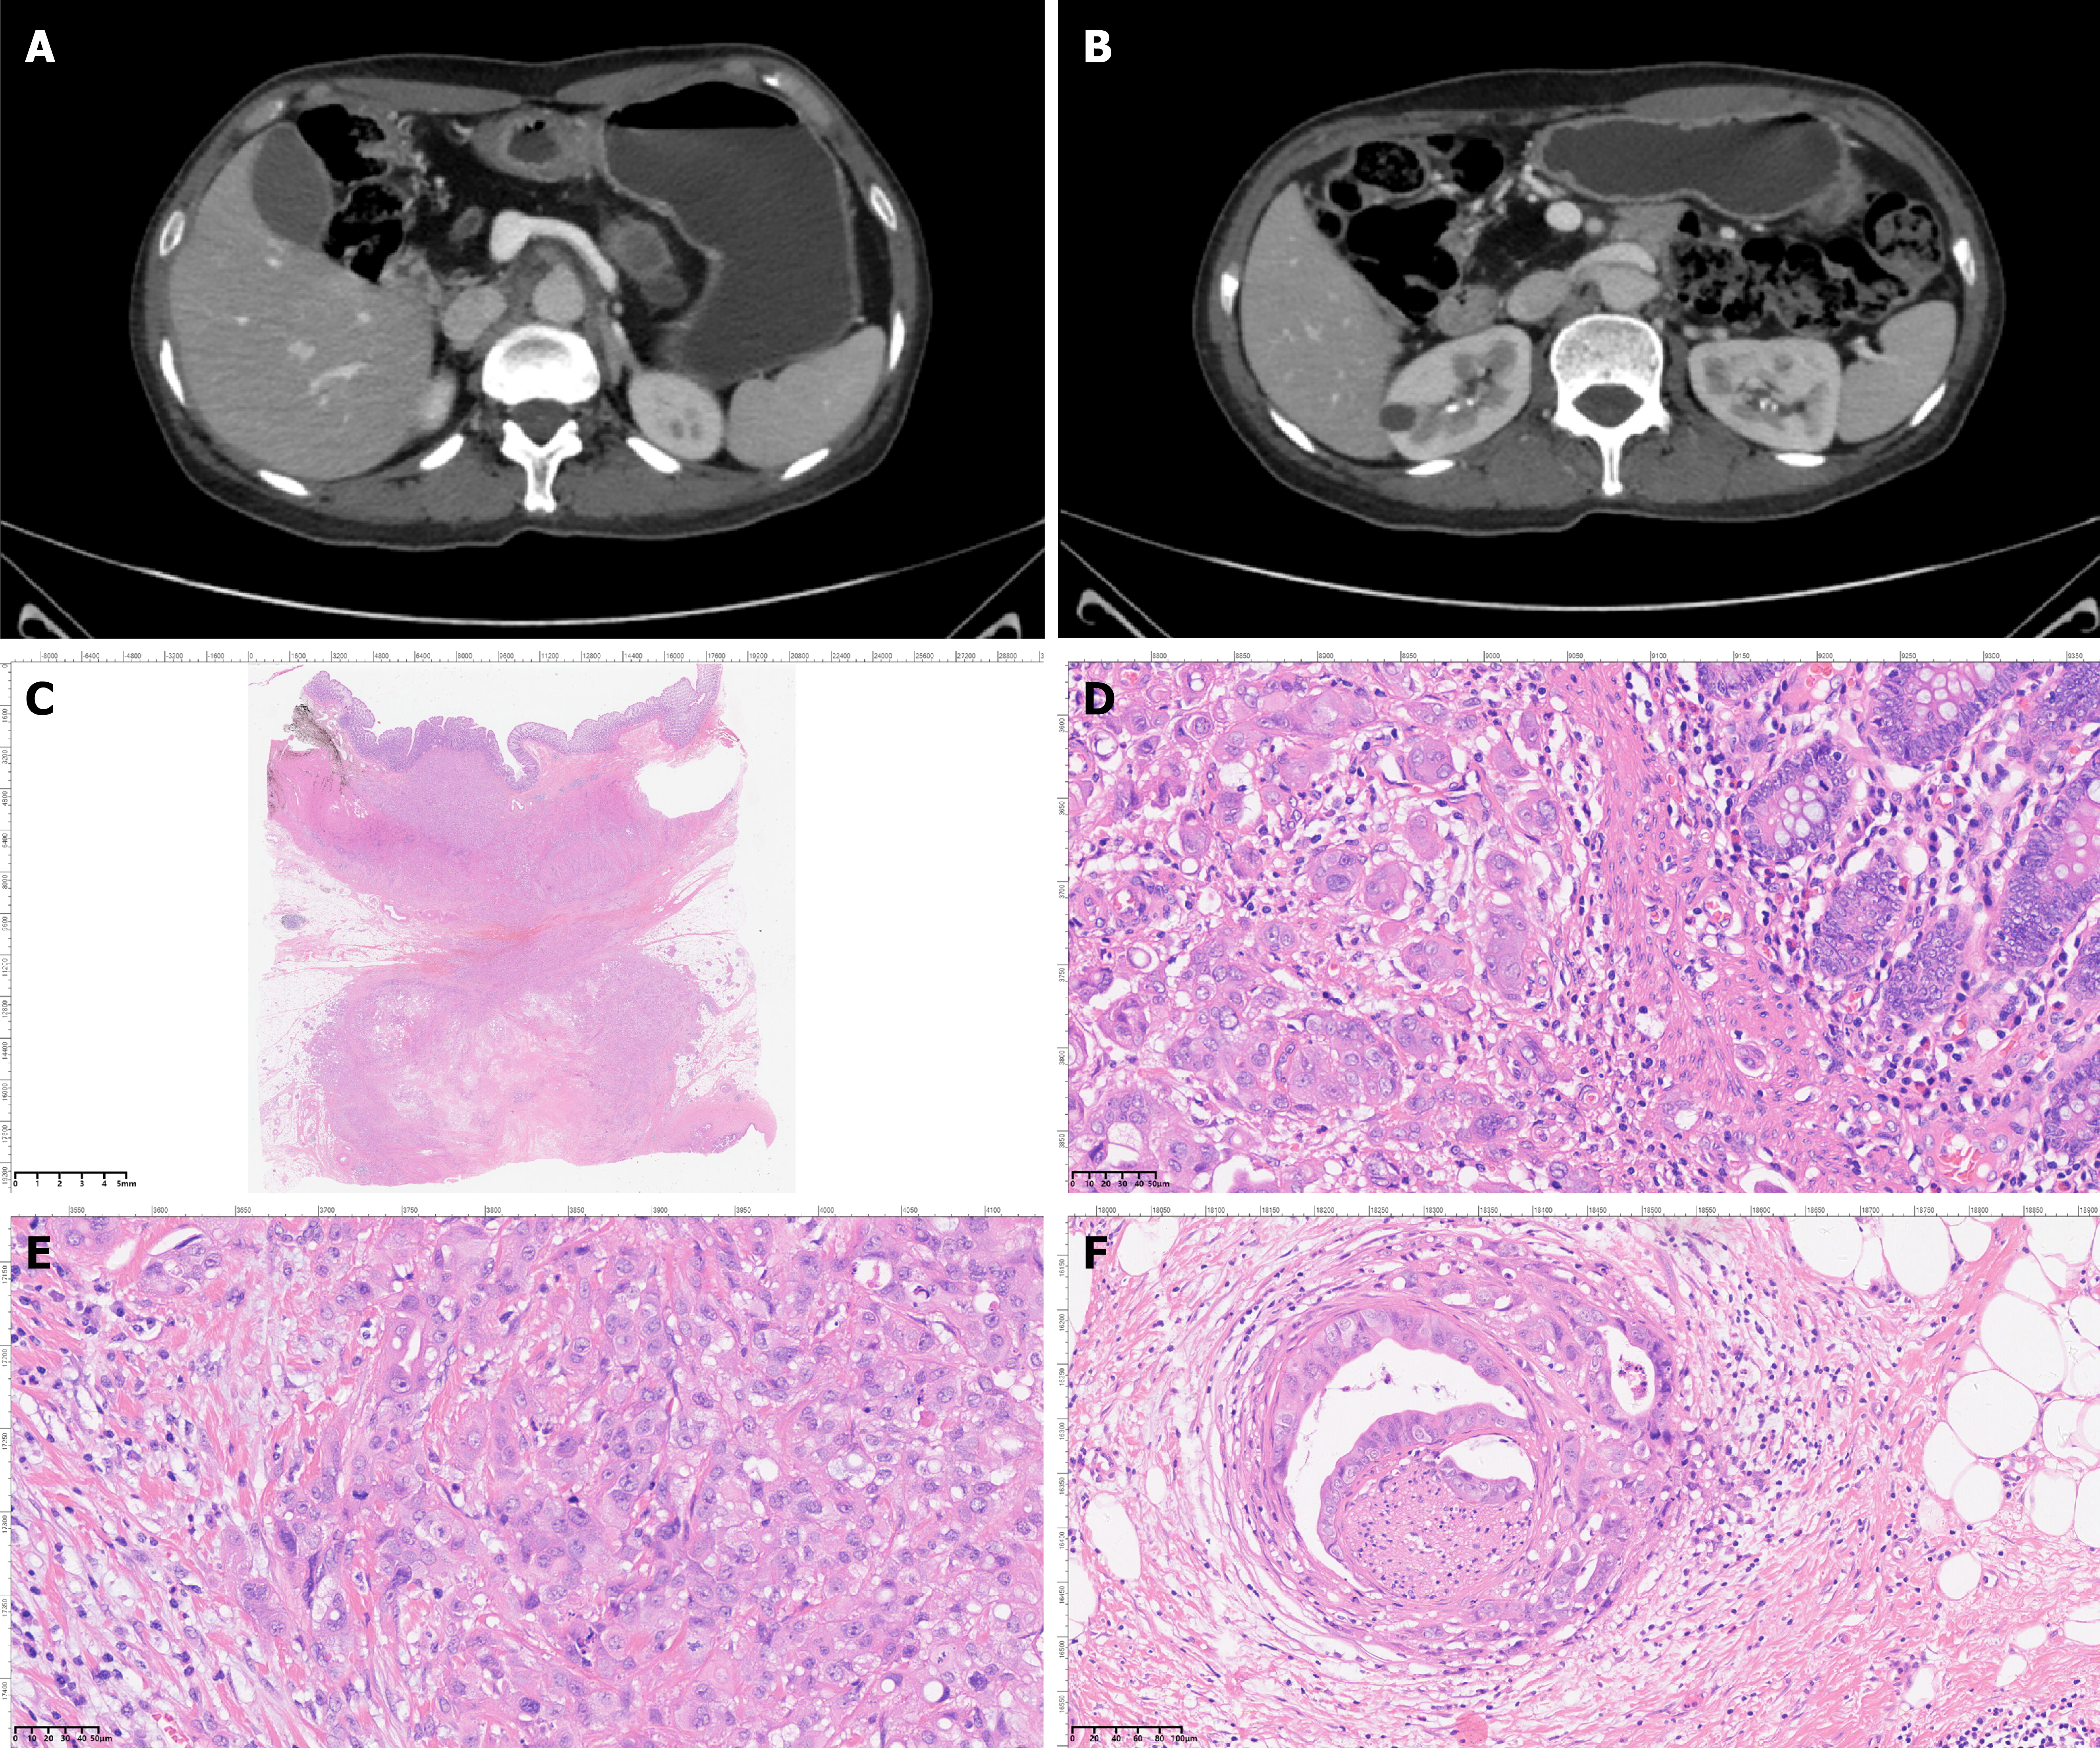

Figure 3 Upper abdomen contrast-enhanced dynamic computed tomography and histopathological analysis of the resected specimen.

A and B: Pancreatic parenchymal atrophy, multiple calcifications in the pancreatic head and body, and a non-enhancing hypodense lesion in the pancreatic tail are observed; C: Malignant tumor cells were observed in the pathological specimen of pancreatic body and tail resection combined with partial colectomy; D: Tumor cell infiltration was observed in the colon; E: A large amount of ductal adenocarcinoma was observed in the pancreas; F: Perineural invasion by carcinoma was observed in the surrounding stroma.